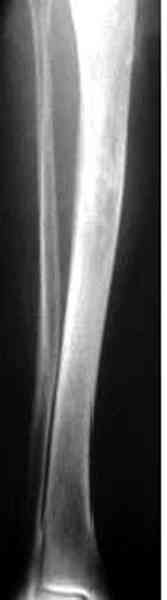

conference мы разбирали похожий случай, ложный сустав большеберцовой кости после резекции опухоли.

К нашему онкологу-ортопеду обратился больной с жалобами на боли в голени, из рассказа - год назад была сделана биопсия большеберцовой кости, но название заболевания "не запомнил”.

В литературе "A Classic Adamantinoma Arising from

Osteofibrous Displasialike Adamantinoma in the Lower Leg: A case report and Review of the Literature похожие снимки.